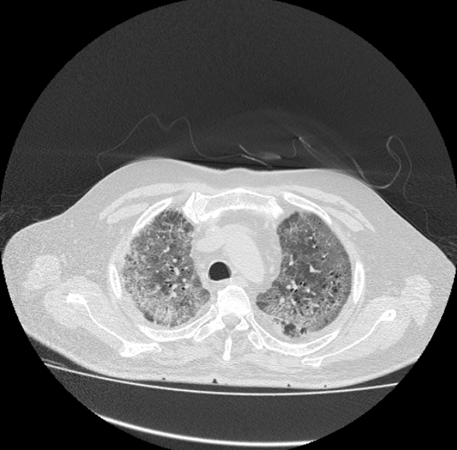

Reticulation as linear consolidation or intralobular density in lungs also reflect the clinical progression of disease in patient's lungs. After GGO and air bronchogram, the presence of reticulation is third most common sign in the patients of COVID-19. It is especially present in the CT images of the patients, which show increasing sensitivity of COVID with time. (Figure 5)

Figure 5 COVID Progression in lungs.

The figure shows rapid increase in the GGO as well as air bronchograms, which shows that with the time COVID is leaving worst impact on the patient’s lungs and thus leading to crazy paving symptoms. This sign is alarming and shows that COVID is going to affect the breathing activities in worst way, if not treated on time. (Figure 6)

Figure 6 Increasing GGO with COVID progression.